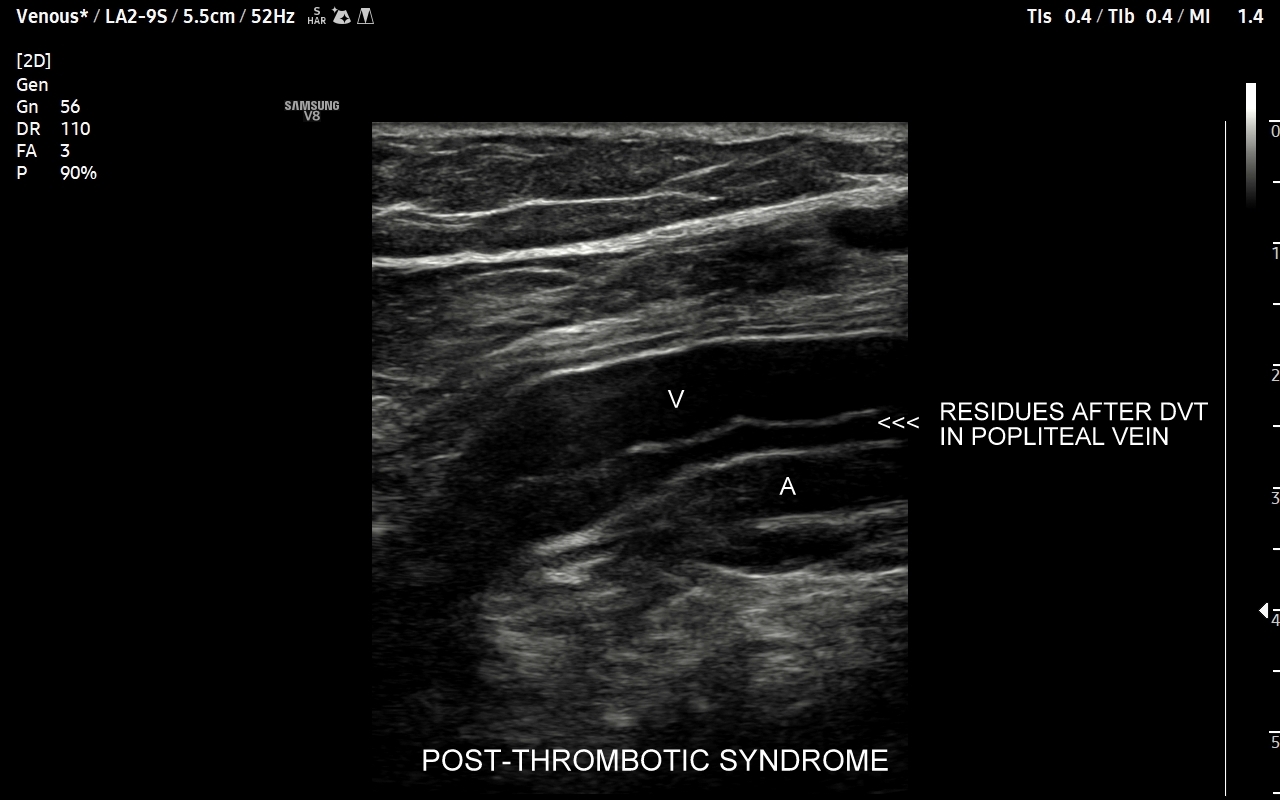

• zespół pozakrzepowy;

Czym jest zakrzepica żył? Zakrzepica żylna polega na powstaniu skrzepu wewnątrz naczynia żylnego i wtórnym rozwoju stanu zapalnego w okolicy naczynia. Choroba dotyczyć może układu powierzchownego żył lub żylaków, a w tym wypadku nie jest zwykle stanem niebezpiecznym; a także układu głębokiego żył, co z kolei jest stanem potencjalnie zagrażającym życiu, gdyż może sprowokować zatorowość płucną. Zakrzepica żył głębokich (ang. deep venous thrombosis DVT) częściej występuje w obrębie żył kończyn dolnych, następnie w obrębie żył biodrowych, rzadziej w żyle podobojczykowej i żyłach głębokich kończyny górnej. Przyczyny zakrzepicy żylnej są różnorodne i obejmują m. in. długie podróże, długotrwałe unieruchomienie, operacje ortopedyczne, chirurgiczne i szczękowe, urazy tkanek miękkich oraz złamania kości, genetycznie uwarunkowane trombofilie, nowotwory złośliwe, odwodnienie, infekcje miejscowe i ogólnoustrojowe. W przypadku zakrzepicy żyły podobojczykowej klasyczną jej przyczyną jest ucisk; w swojej praktyce klinicznej dr Szczepański spotkał się z zakrzepicą podobojczykową wywołaną m. in. przez ciężki plecak, wyciskanie sztangi na siłowni, czy przez uprawianie wspinaczki skałkowej. W warunkach szpitalnych zakrzepica żyły podobojczykowej lub żyły szyjnej wewnętrznej może pojawić się w wyniku zakładania cewników dożylnych. Sprawne wykrycie zakrzepicy w badaniu USG, a następnie wdrożenie odpowiedniej terapii uchronić może pacjenta przed powikłaniami ostrymi (np. zator płucny), jak i opóźnionymi (np. zespół pozakrzepowy).

Badanie USG żył kończyn dolnych najczęściej wykonywane jest w ramach diagnostyki niewydolności żył powierzchownych oraz ich objawów w postaci pajączków żylnych, żylaków kończyn dolnych, obrzęków i owrzodzeń żylnych. Kolejnym pod względem częstości wskazaniem do badania Doppler żył jest podejrzenie zakrzepicy żył głębokich kończyn dolnych, monitorowanie leczenia zakrzepicy oraz ocena jej powikłań odległych. Powikłaniem nieleczonej zakrzepicy żył głębokich może być zespół pozakrzepowy manifestujący się masywnymi obrzękami kończyny i zaburzeniami troficznymi. Badanie USG Doppler żył kończyn dolnych często uzupełniane jest oceną układu żył centralnych w miednicy i jamie brzusznej. W tych obszarach również pojawiać się mogą żylne zmiany zakrzepowe, niedrożności żył, a nawet zmiany nowotworowe.